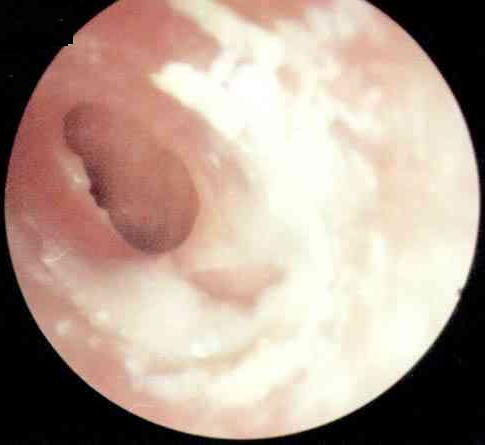

卡他性中耳炎病理图

当咽鼓管功能障碍时,外界控制不能进入中耳,中耳内原有的气体逐渐被粘膜吸收,腔内形成相对负压,引起中耳粘膜静脉扩张、淤血、血管壁通透性增强,鼓室内出现漏出液。如负压不能得到解除,中耳粘膜可发生一系列病理变化,主要表现为上皮增厚,上皮细胞化生,鼓室前部低矮的假复层柱状上皮变为增厚的纤毛上皮,鼓室后部的单层扁平上皮变为假复层柱状上皮,杯状细胞增多;分泌亢进,上皮下病理性腺体组织形成,固有层血管周围出现以淋巴细胞及浆细胞为主的圆形细胞浸润。疾病恢复期,腺体逐渐退化,分泌物减少,粘膜渐恢复正常。